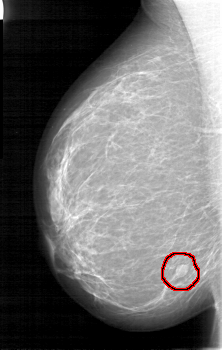

D_4090_1.RIGHT_CC

RIGHT_CC LINES 5281 PIXELS_PER_LINE 3226 BITS_PER_PIXEL 12 RESOLUTION 43.5 OVERLAY

FILE: D_4090_1.RIGHT_CC.OVERLAY

TOTAL_ABNORMALITIES 1

ABNORMALITY 1

LESION_TYPE MASS SHAPE OVAL MARGINS ILL_DEFINED

ASSESSMENT 0

SUBTLETY 5

PATHOLOGY BENIGN

TOTAL_OUTLINES 1

BOUNDARY